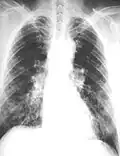

The abnormal chest x-ray and its interpretation remain the most important factors in establishing the presence of pulmonary fibrosis.[11] The findings usually appear as small, irregular parenchymal opacities, primarily in the lung bases. Using the ILO Classification system, "s", "t", and/or "u" opacities predominate. CT or high-resolution CT (HRCT) are more sensitive than plain radiography at detecting pulmonary fibrosis (as well as any underlying pleural changes). More than 50% of people affected with asbestosis develop plaques in the parietal pleura, the space between the chest wall and lungs. Once apparent, the radiographic findings in asbestosis may slowly progress or remain static, even in the absence of further asbestos exposure.[26] Rapid progression suggests an alternative diagnosis.

Asbestosis resembles many other diffuse interstitial lung diseases, including other pneumoconiosis. The differential diagnosis includes idiopathic pulmonary fibrosis (IPF), hypersensitivity pneumonitis, sarcoidosis, and others. The presence of pleural plaques may provide supportive evidence of causation by asbestos. Although lung biopsy is usually not necessary, the presence of asbestos bodies in association with pulmonary fibrosis establishes the diagnosis.[27] Conversely, interstitial pulmonary fibrosis in the absence of asbestos bodies is most likely not asbestosis.[11] Asbestos bodies in the absence of fibrosis indicate exposure, not disease.

61-year-old working industrially with asbestos for decades